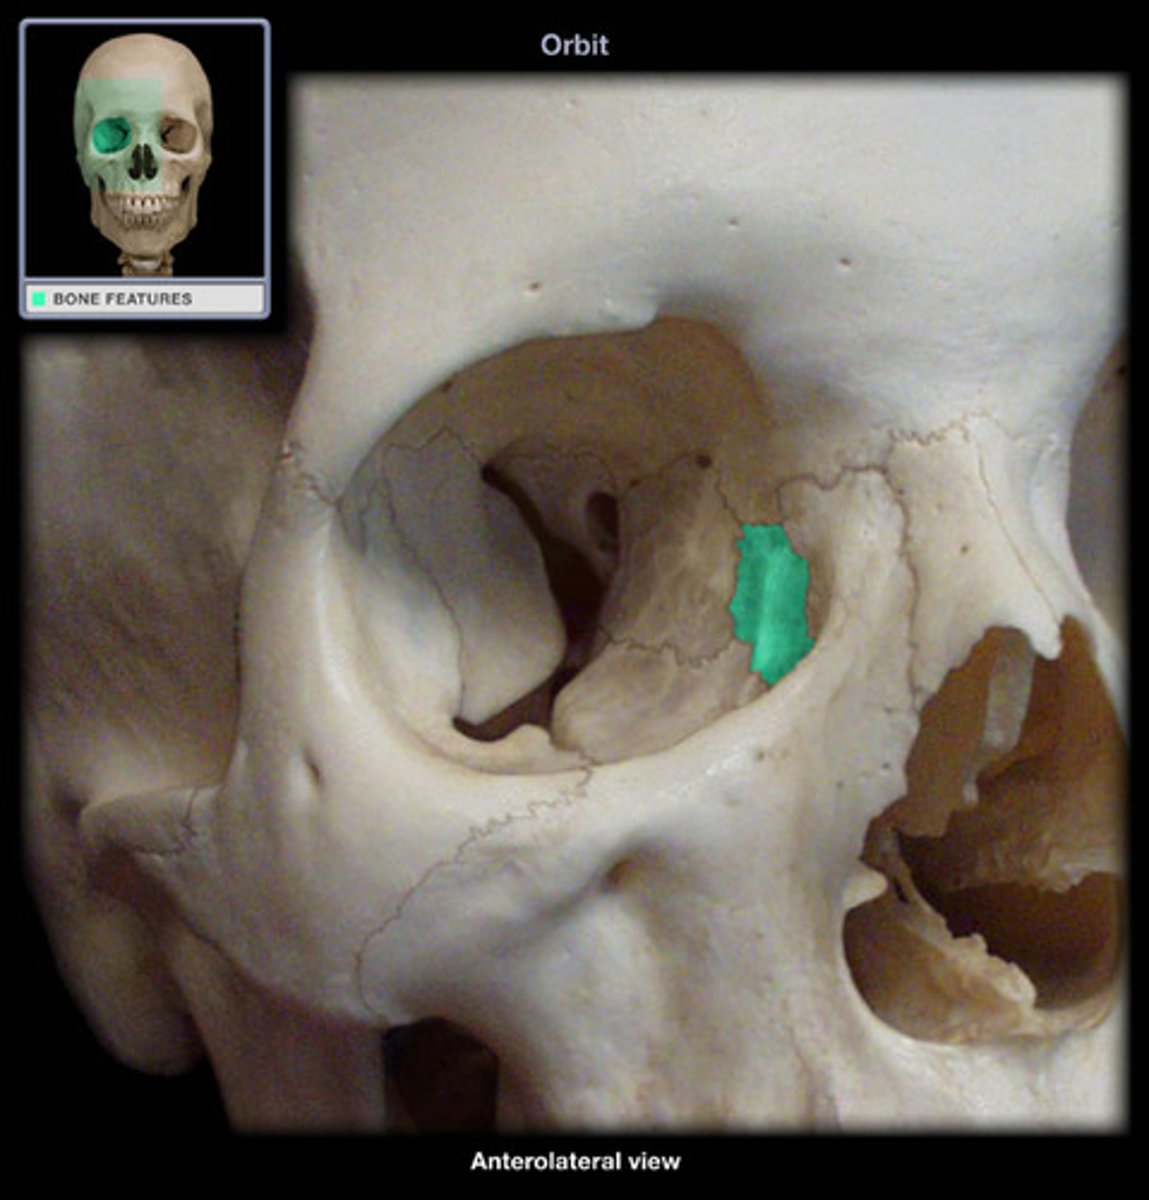

What is B

frontal bone

What is A

ethmoid

What is C

sphenoid

what is D

Palatine

What is E

Zygoma

What is F

Maxilla

What is G and H

optic foramen in orbit

sphenoid strut